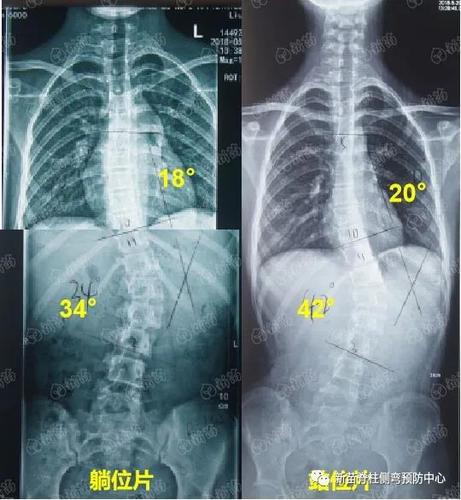

胸椎侧弯